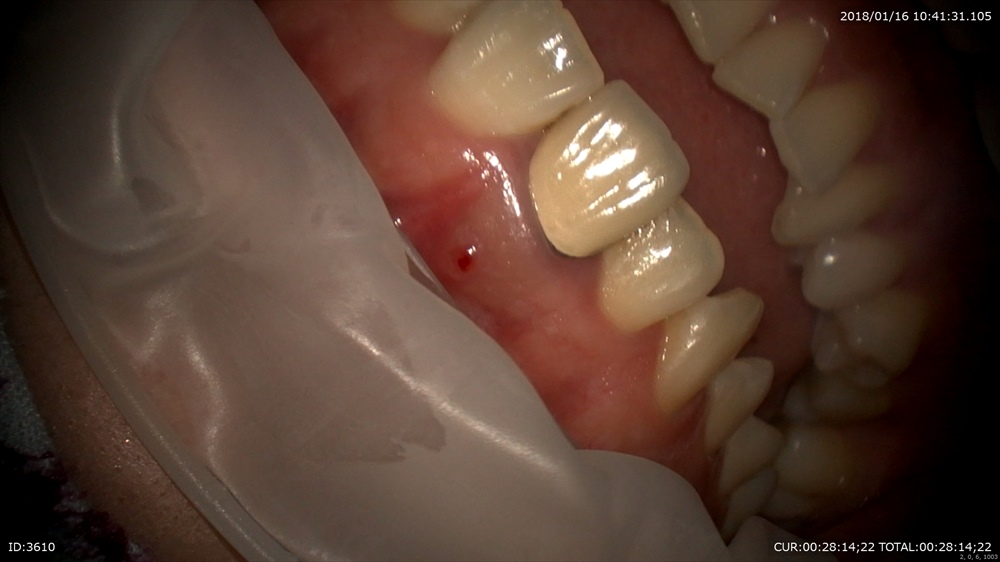

このケースも 歯茎から膿が!!根管治療で抜歯を回避します。

ここまで根管治療が始まってから3回。1回の時間をしっかりとることで数回でかめるようになりました。この方は他院での根管治療が治らず去年来院。悩まれていましたが症状が消え笑顔が戻りました。

治療は回数を重ねるほど細菌感染の機会にさらされます。だから